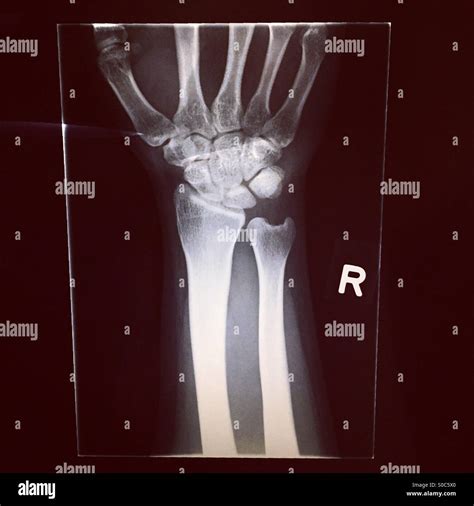

• X-rays: X-rays are the primary imaging tool used to confirm the presence and type of fracture. They provide detailed images of the bones and can help determine the severity of the injury.

Carpal Fractures Fractures in the carpals, which are the small bones of the wrist. Falls onto an outstretched hand, sports injuries, or direct impact.